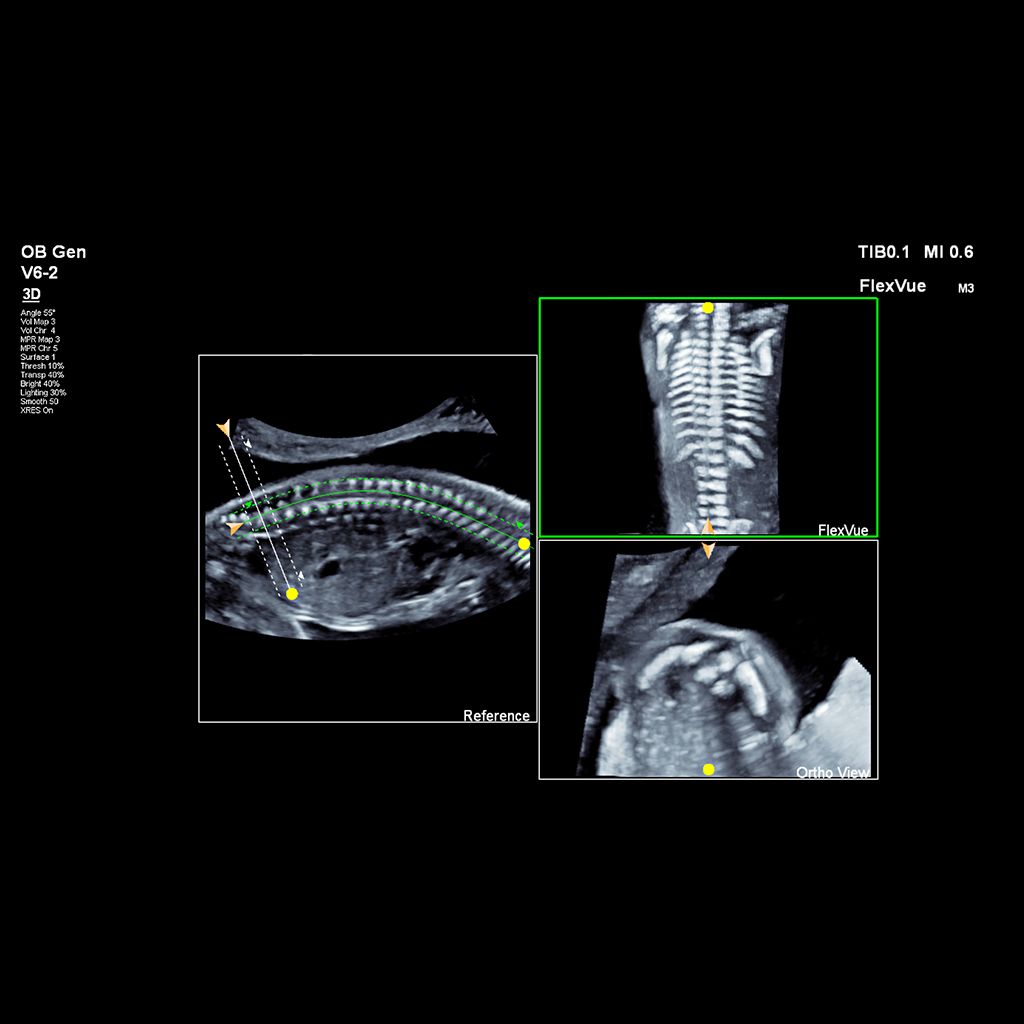

Demonstrated results using FlexVue

It (FlexVue) takes all of the complications out of MPR and manipulation of a surface-rendered volume. By deploying a straight line or a curved trace or continuous trace, we can take a curved image, flatten it out and make it a single planar image.